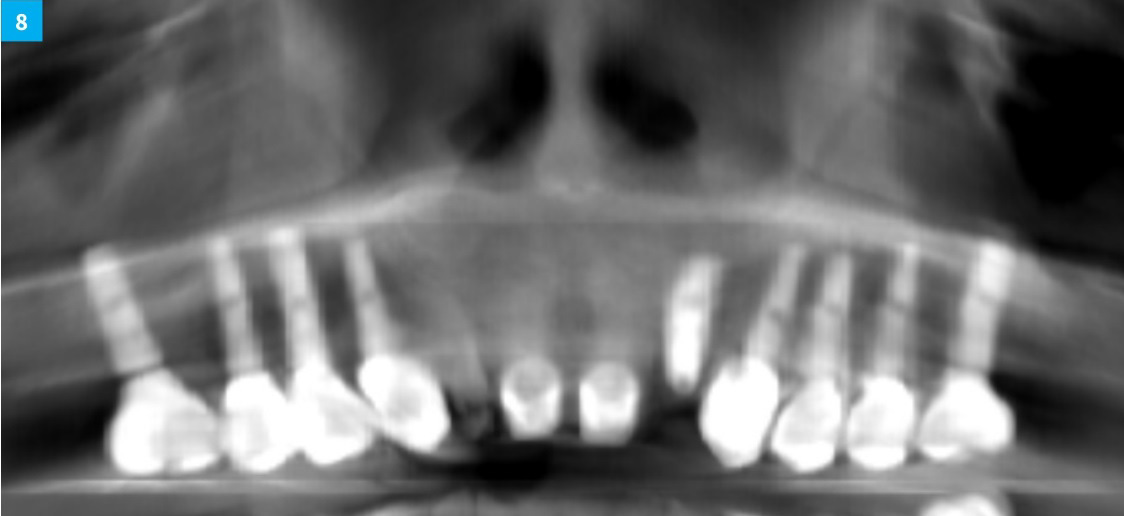

Dental Implant Continuum with DSI implants and products. Case 6